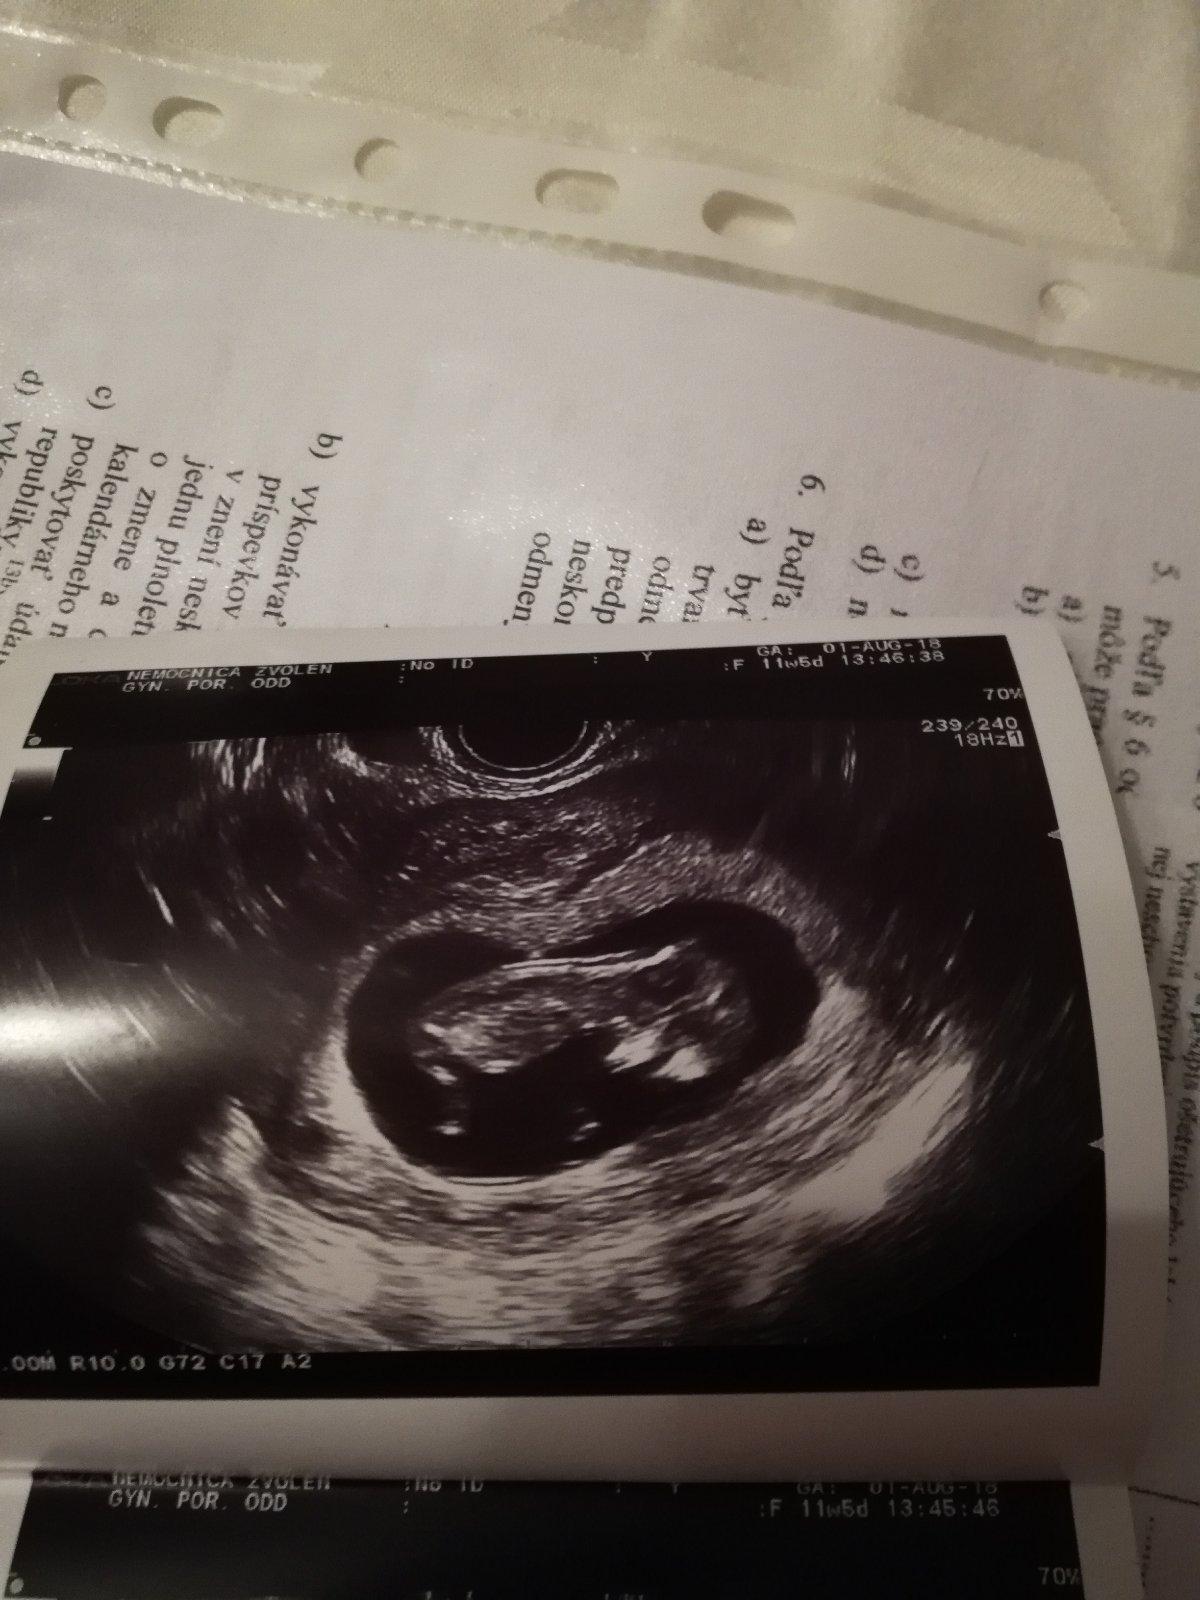

@vejkazvejka to sa nedá nemyslieť na to, skončíš ako ja, bude ti hrabkať 😁 ja som dnes bola na screeningu a takúto fotečku som dostala